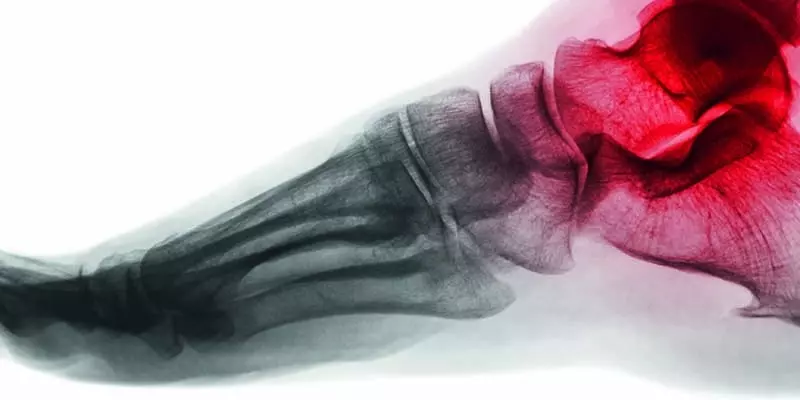

Współcześnie dokonuje się radykalna zmiana rozumienia mechanizmu działania systemu mięśniowo-szkieletowego. Coraz bardziej oczywiste jest, że znana do tej pory koncepcja mięśni jest przestarzała i niefizjologiczna. Wizja powięzi, jako wszechobecnego systemu regulacji organizmu, niesie następną generację efektywnych technik manualnych. Nieco czasu upłynie, zanim to nowe spojrzenie na sposób organizacji żywego organizmu pojawi się w podręcznikach. Ich autorzy, przyzwyczajeni do modelu mięśni poruszających szkielet, muszą zrozumieć, w jaki sposób działa mechanizm ruchu. Terapeuci manualni mogą skrócić ten czas oczekiwania i już teraz skorzystać z wyników nowych badań naukowych.

Zmiana modelu postrzegania tego mechanizmu częściowo wywodzi się z nowych badań z zakresu neurologii ruchu (które stawiają pod znakiem zapytania najbardziej zaufane koncepcje) i z bardzo dokładnie opisanych w „The Brain that Changes Itself” Normana Doidge’a (//www.normandoidge.com) odkryć właściwości plastycznych sieci połączeń nerwowych. Kolejnym elementem wpływającym na odmienne ujmowanie tego zagadnienia jest wzrost liczby badań nad właściwościami matrycy pozakomórkowej oraz traktowanych do tej pory po macoszemu tkanek łącznych. Wyniki tych nowych badań naukowych prezentowane są na Fascia Research Congress.